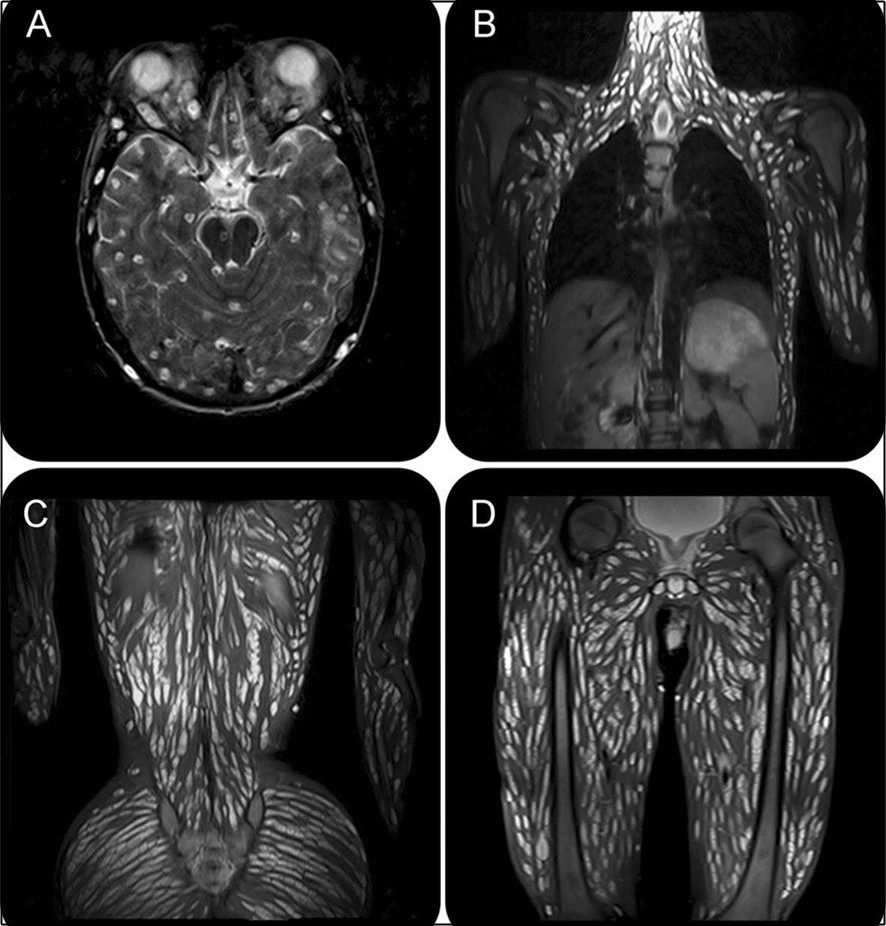

Sán dây phủ kín cơ thể.

Sau những chẩn đoán ban đầu, bác sĩ cho tiến hành chụp cộng hưởng từ MRI và phát hiện ra mô não, đầu, ngực, bụng và chân tay của bệnh nhân phủ đầy sán dây, trông cực kỳ khủng khiếp. Bệnh nhân được xác nhận là nhiễm cysticercosis (bệnh nhiễm ấu trùng sán dây lợn).

Qua tìm hiểu, bác sĩ biết được rằng bệnh nhân đã ăn thịt heo chín tái hoặc chưa chín kỹ cùng với rau, trứng, trái cây. Và rất có thể tay của bệnh nhân không sạch sẽ nên mới dẫn tới tình trạng sán dây phủ kín cơ thể như vậy.

May mắn thay, bệnh nhân được điều trị bằng một loạt thuốc chống giun, steroid và thuốc chống động kinh. Sau đó, tình hình của chàng trai này đã cải thiện đáng kể.